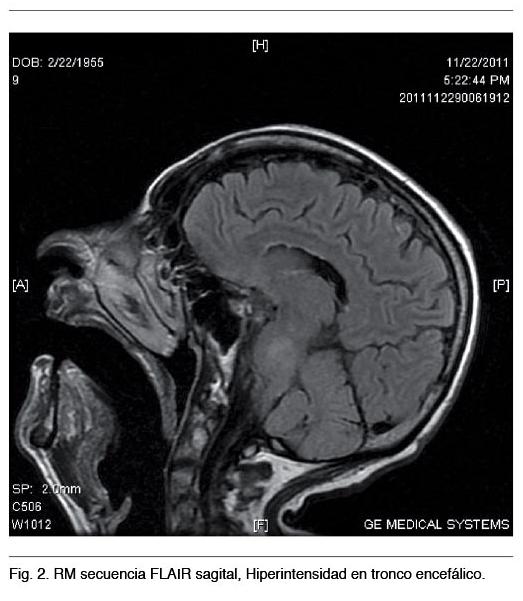

La imagenología, especialmente la Resonancia Nuclear Magnética (RNM), ha contribuido a mejorar el diagnóstico por las imágenes características de afectación del cuerpo calloso (1) que ofrecen las diferentes secuencias; aumento de señal del cuerpo calloso en T2 y FLAIR o zonas quísticas en T1 sagital con disminución de señal (3). Las alteraciones en la RNM pueden extenderse a otras regiones de la sustancia blanca (1,11). La Tomografía Computada (TC) craneal puede captar una hipodensidad en la rodilla del cuerpo calloso pero dado que los cortes suelen ser exclusivamente axiales no es infrecuente que la alteración del cuerpo calloso pase desapercibida (12). Los análisis de casos a través de la imagenología han revelado varios patrones, incluyendo lesiones dispersas o quistes observados a lo largo del cuerpo calloso, áreas cercanas (comisuras anterior y posterior, vías de la sustancia blanca, etc.) y el centro semioval. En algunos pacientes la EMB puede estar asociada a daño cortical, en general en el área frontal lateral y lóbulo temporal, principalmente en la tercera capa cortical. En dichas regiones las neuronas son sustituídas por células gliales (2). En 1939 Morel describió esta esclerosis laminar cortical, denominada esclerosis laminar cortical de Morel (2).

RNM mostró en diferentes secuencias lesiones típicas en cuerpo calloso y tronco encefálico (Figuras 1 y 2).

Este caso clínico a forma de presentación subaguda, muestra varias similitudes con respecto a los publicados en la literatura (18-20): el antecedente de alcoholismo crónico, síntomas y signología neurológica poco característica y el diagnóstico por neuroimagen con la afectación típica del cuerpo calloso y el compromiso de otras estructuras neurológicas.

En cuanto a las diferencias con la mayoría de los casos revisados se presentó en el sexo femenino con lesión pontina por RM, sin evidencia clínica de dicha afectación (21,22).

Asimismo la mielinólisis pontina puede coexistir con esta enfermedad e histológicamente es similar a la mielinólisis osmolar, por lo que se supone una patogenia común (21,22).